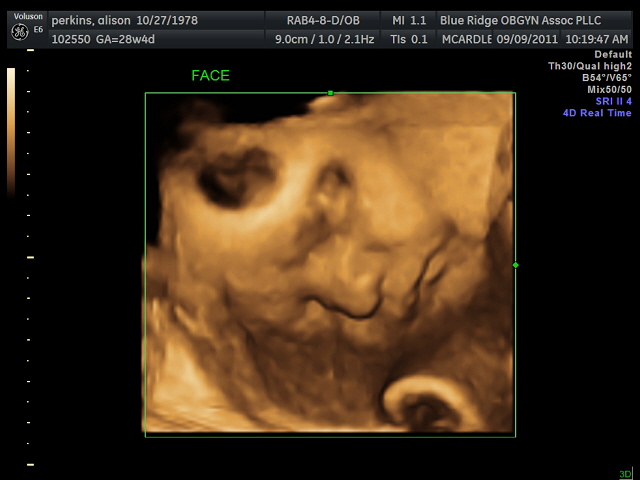

3D Ultrasound!